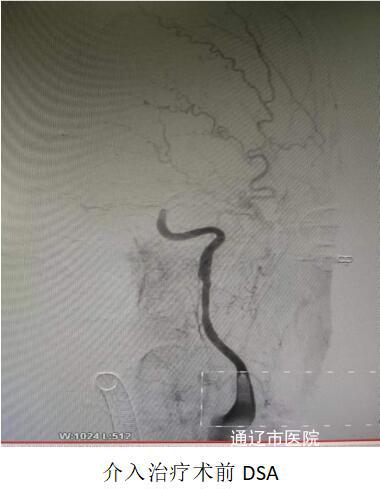

患者进入导管室时,已呈现昏迷状态,介入组医师实施紧急抢救,手术中可见左侧颈内动脉起始处存在巨大血栓,血栓负荷较大,予以支架取栓结合抽吸治疗后,血管实现完全再通;同步为患者的颈内动脉起始段植入支架进行血管内治疗,从根本上解除患者此次发病的隐患。术后转至NCU病房,意识转清,生命体征恢复平稳,四肢功能基本恢复如前,现已顺利转入普通病房进行下一步治疗。